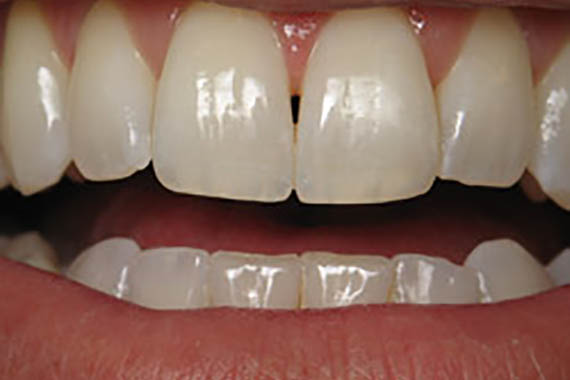

Crowns

Before

After